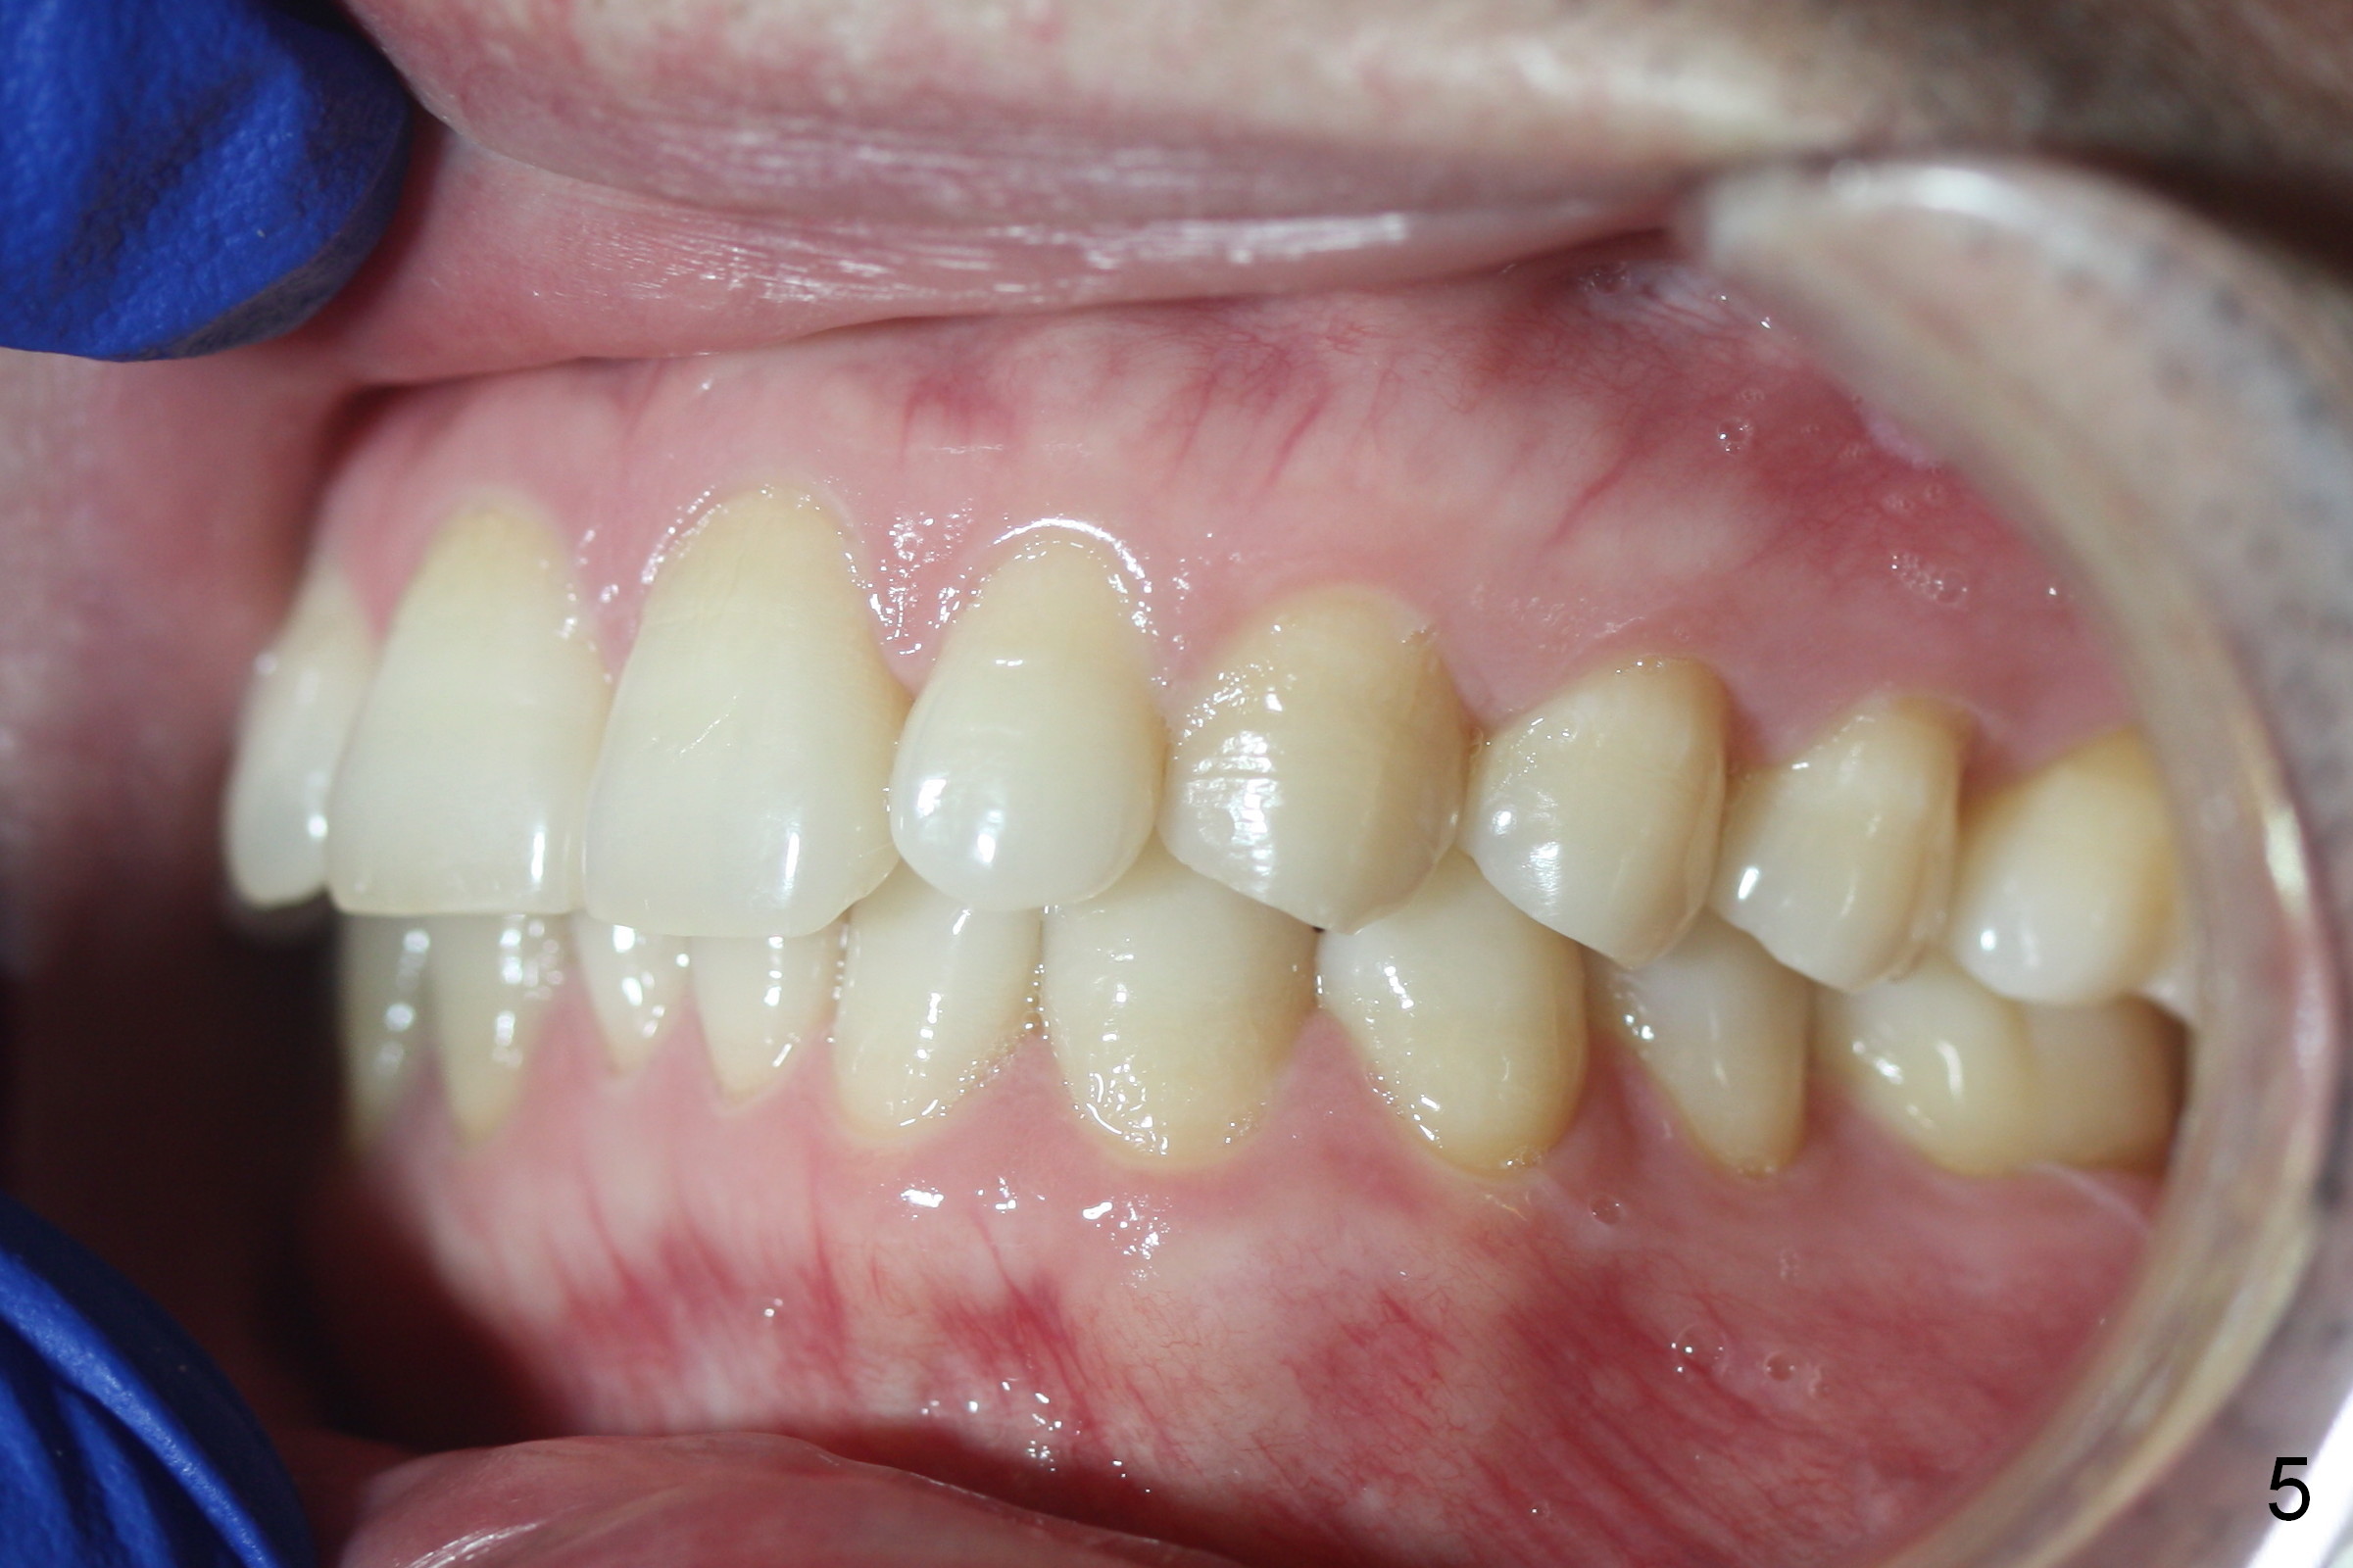

A 42-year-old man requests orthodontic treatment after extraction of the teeth #1, 16, 17, and 32, because it is easier for him to maintain oral hygiene post extraction. He thinks that orthodontic treatment will do the same. He appears to care about his dental alignment: not showing his teeth while smiling (Fig.2). The facial profile is within normal limit (Fig.3). His lower anterior teeth are moderately crowded (Fig.4) with anterior deep overbite and overjet (Fig.5,6). The deep overbite is more appreciated when the model is viewed posteriorly (Fig.7), approximately 90% of the upper incisors are covered by the lower anterior ones. More lingual surfaces are shown in another case before (Fig.8) and after (Fig.9) orthodontic treatment. With differential placement of brackets on the canines vs. incisors (Fig.6), the deep bite should be able to be corrected. Proximal reduction may be necessary.